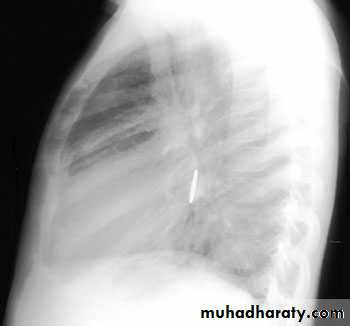

Expiratory chest radiograph in a 12-month-old boy with a 2-month history of wheezing demonstrates continued hyperlucency and hyperexpansion of the right hemithorax.